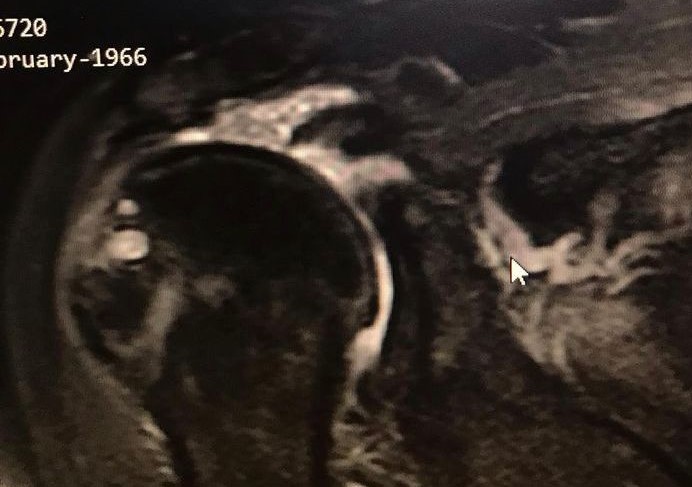

Preoperatif omuz MRI — masif yırtık